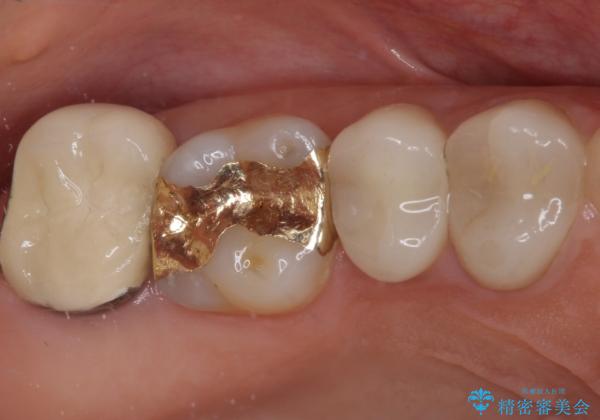

ゴールドインレーは銀歯のインレーやセラミックインレーと比べ、「技工操作の精度が高く、適合が著しく良い」というメリットがあります。特に上の奥歯は歯科医師の操作が行いにくいため、「適合の良さ」は再治療のリスクを防ぐ上でとても重要な要素となります。

上の奥歯は金属色が見えることもないため、審美的な問題は全くありません。

咬合力が原因と思われるむし歯治療では、ゴールドインレーが第一選択になるといっても良いかもしれません。